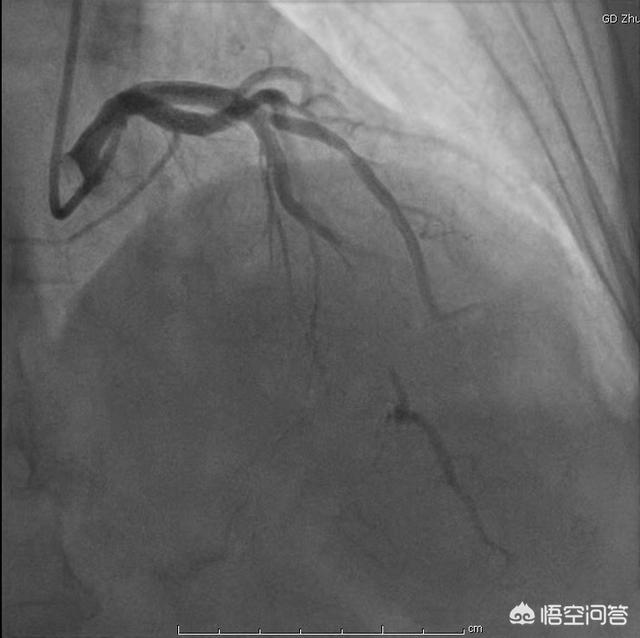

冠動脈疾患、すなわち冠状動脈性心疾患は、様々な理由による冠動脈の狭窄や閉塞による心筋虚血、低酸素、壊死によって引き起こされる。一般に、冠動脈の狭窄の程度が50%以上になると冠動脈性心疾患と診断される。冠動脈疾患患者の診断は主に胸部圧迫感や胸痛などの臨床症状に依存し、冠動脈造影などの検査によって明らかにされる。

まず、いわゆる冠状動脈性心疾患とは、冠状動脈の血液供給量と心臓の酸素消費量のバランスが崩れ、心筋が一時的あるいは持続的に虚血や低酸素状態に陥り、その結果、狭心症、梗塞、不整脈、心不全などが心臓病の臨床症状として現れることを指す。冠状動脈性心臓病の一般的な病態生理学的基礎は冠状動脈アテローム性動脈硬化症であり、冠状動脈性心臓病の診断は主に冠状動脈CTAまたは冠状動脈造影の結果に依存し、冠状動脈アテローム性動脈硬化症の程度が50%以上の内腔狭窄の程度に達した場合、冠状動脈性心臓病と診断することができます;冠状動脈のアテローム性動脈硬化症があるが、50%未満の狭窄は冠状動脈アテローム性動脈硬化症と診断されます。

臨床の現実は、患者の症状や冠動脈疾患の原因(高血圧、糖尿病、高脂血症など)をもとに冠動脈疾患を診断することができる。もちろん、冠動脈造影や冠動脈CTAの結果があれば、それはより直感的なものになるだろう。

冠動脈の閉塞の程度は、冠動脈疾患患者がそのリスクを評価するための最も直感的なデータである。冠動脈疾患の診断を確定するための現在最も権威のある基準は50%の狭窄である。しかし、そのデータは冠動脈造影から得られたものでなければならず、冠動脈CTから得られたものであってはならない。